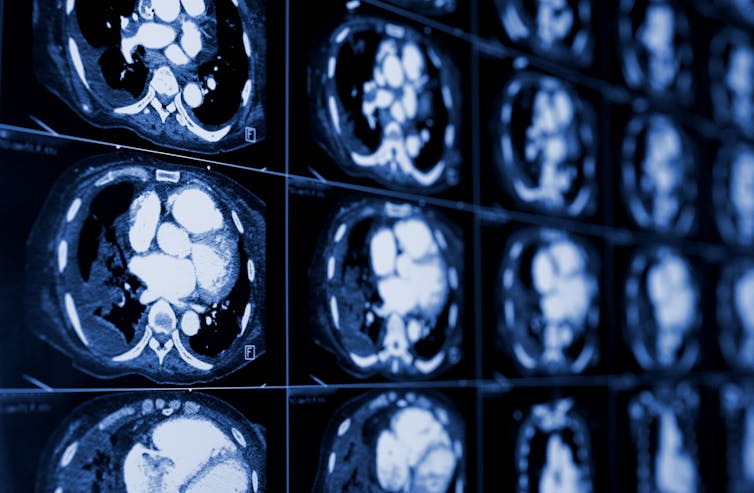

Low-dose CT scan for lung cancer

Lung cancer screening involves a yearly low-dose computed tomography, or CT, scan, a diagnostic imaging tool that uses X-rays to create detailed cross sections of the inside of the body. Screening 250 patients can prevent one lung cancer death. In comparison, 645 people screened with a mammogram can prevent one breast cancer death.

Some people have reservations surrounding the scan itself because of radiation exposure. The radiation from a low-dose CT scan, however, is about 1.4 millisieverts – the scientific unit used to measure ionizing radiation – which is less than the 3 to 5 millisieverts of background radiation a person may be exposed to in a given year on average while living on Earth.

The whole process takes only a few minutes and does not require any needles, medications or infusions. During the scan, the patient lies on the scanner’s sliding table and raises their arms above their head. The technologist may ask them to hold their breath for 5 to 10 seconds as the table passes through the scanner.

A radiologist summarizes the results of the test for their doctor in a report. If the result is negative for findings in the lungs, the patient would return in one year for another scan. If the result is positive, it usually means the radiologist saw a lung nodule, or a spot on the lung. Not all lung nodules are cancer, and patients may require additional imaging or a biopsy to confirm.